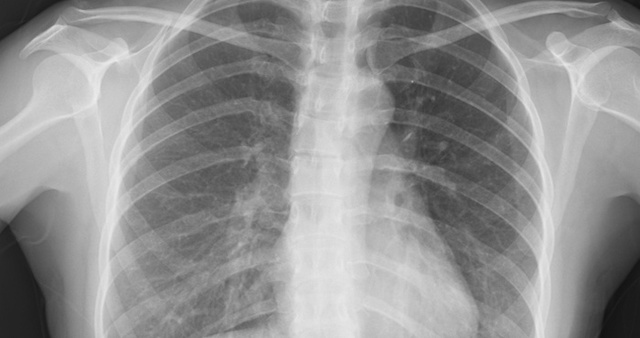

• Medical Imaging

Medical Imaging

The first instance of machines that produced medical imaging were X-rays. The X-ray was ‘accidently’ invented in 1895 by German physicist Wilhelm Conrad Rӧntgen when experimenting with electrical currents through glass cathode-ray tubes.